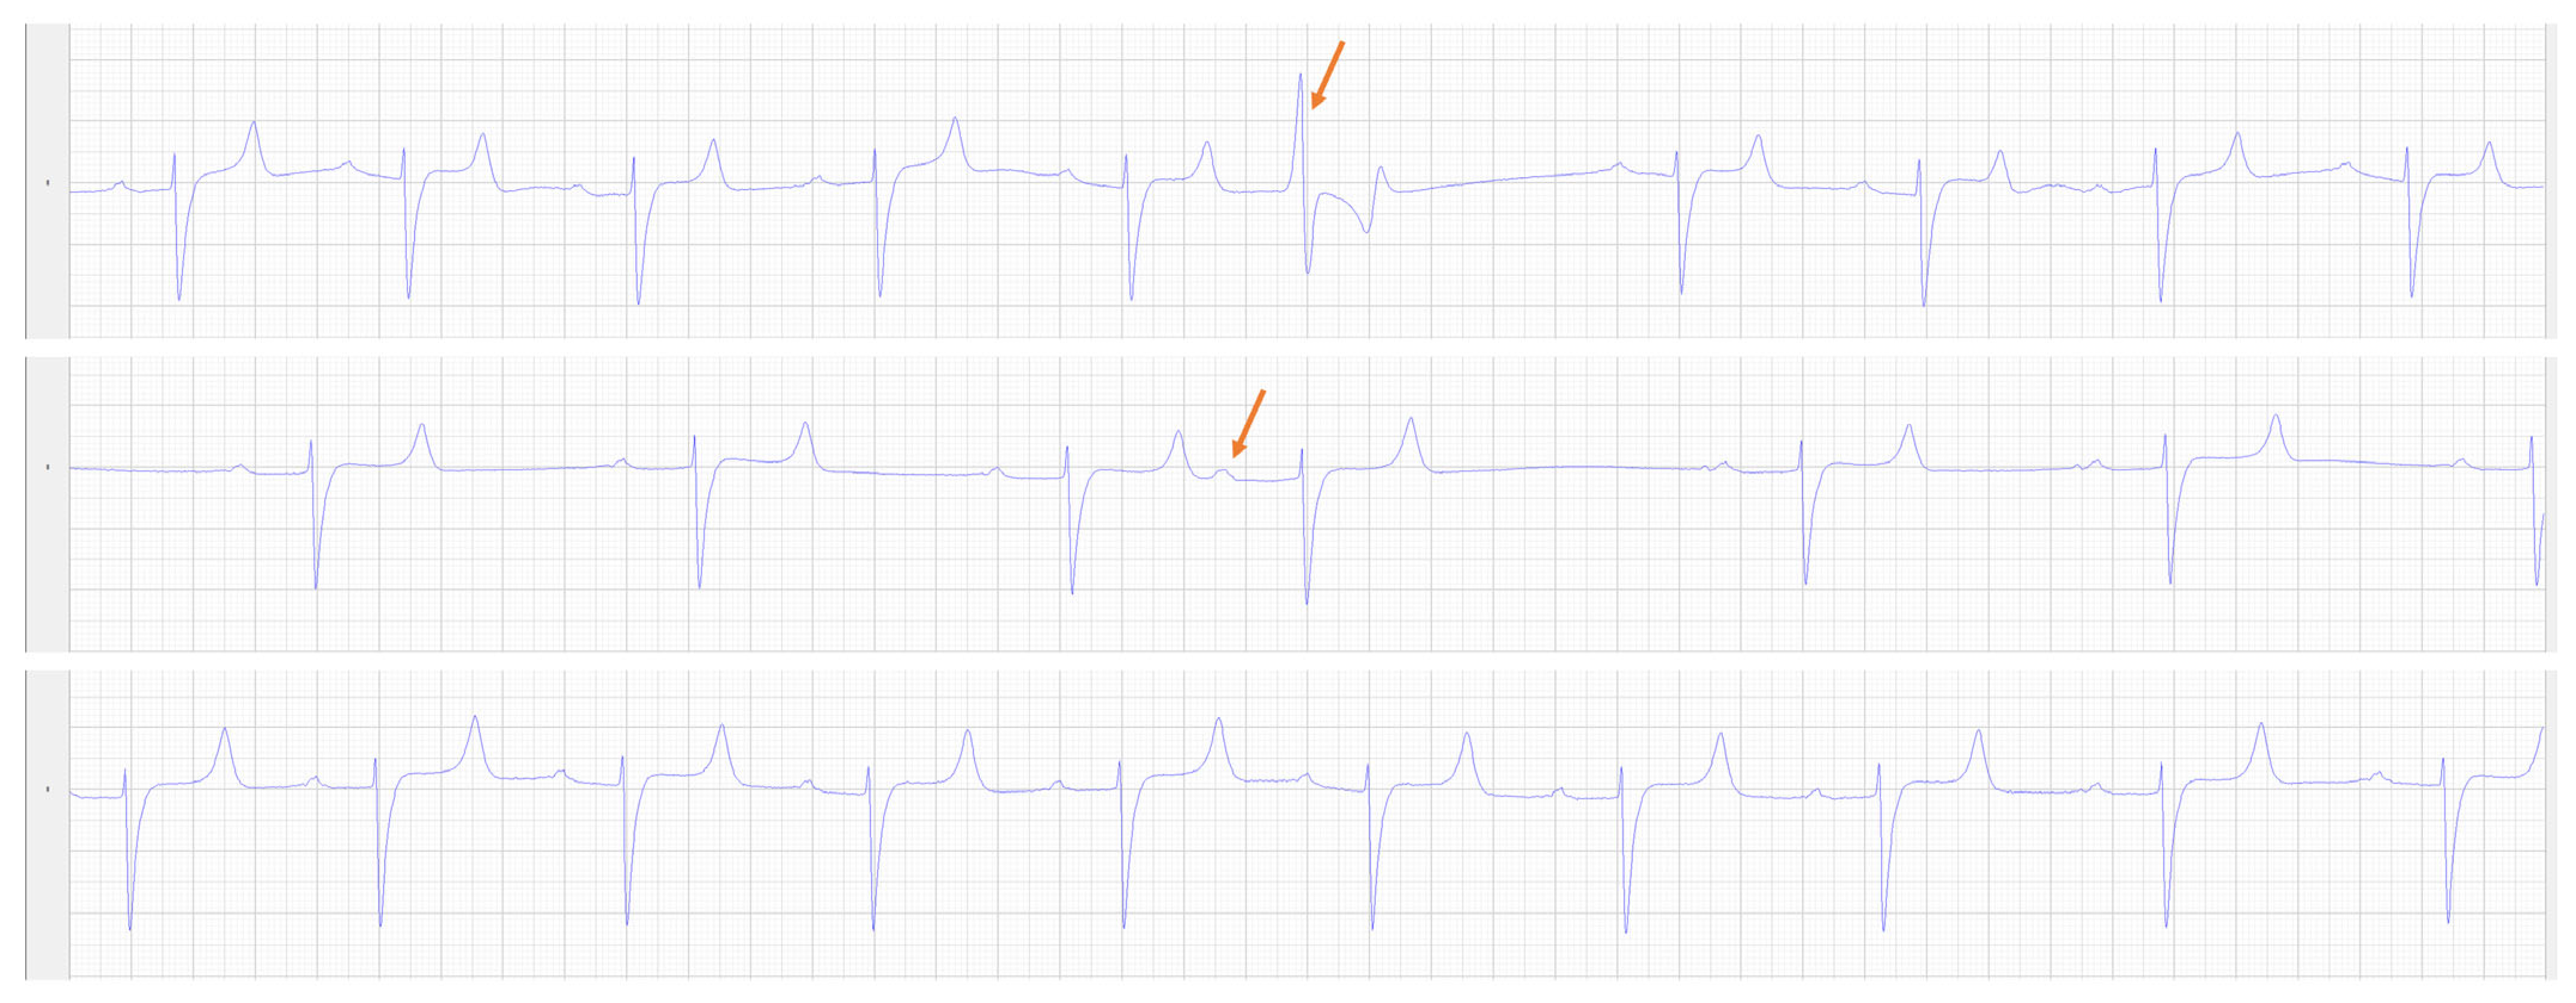

2.2. Pre-Operative Diagnostic Testing

3.1. Post-Operative Diagnostics